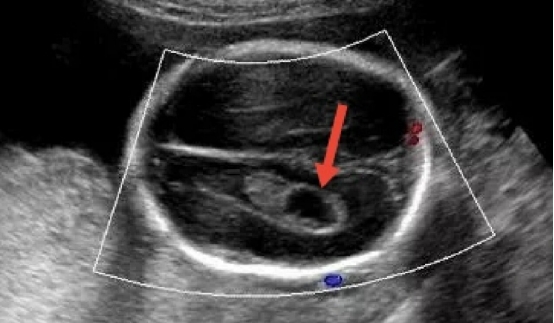

4. 脉络丛囊肿(CPC)

1)是什么?胎儿大脑脉络丛(产生脑脊液的结构)内出现的充满脑脊液的“小囊肿”。

2)意味着什么?绝大多数(超过95%)脉络丛囊肿在孕晚期会自行消失,且不引起任何问题。它也与18-三体综合征的风险增加有关。

3)怎么办?如果它是孤立性的,且其他筛查结果(如唐筛/NIPT)低风险,通常被视为正常变异,无需担心。如果合并其他异常,则需进行遗传咨询。